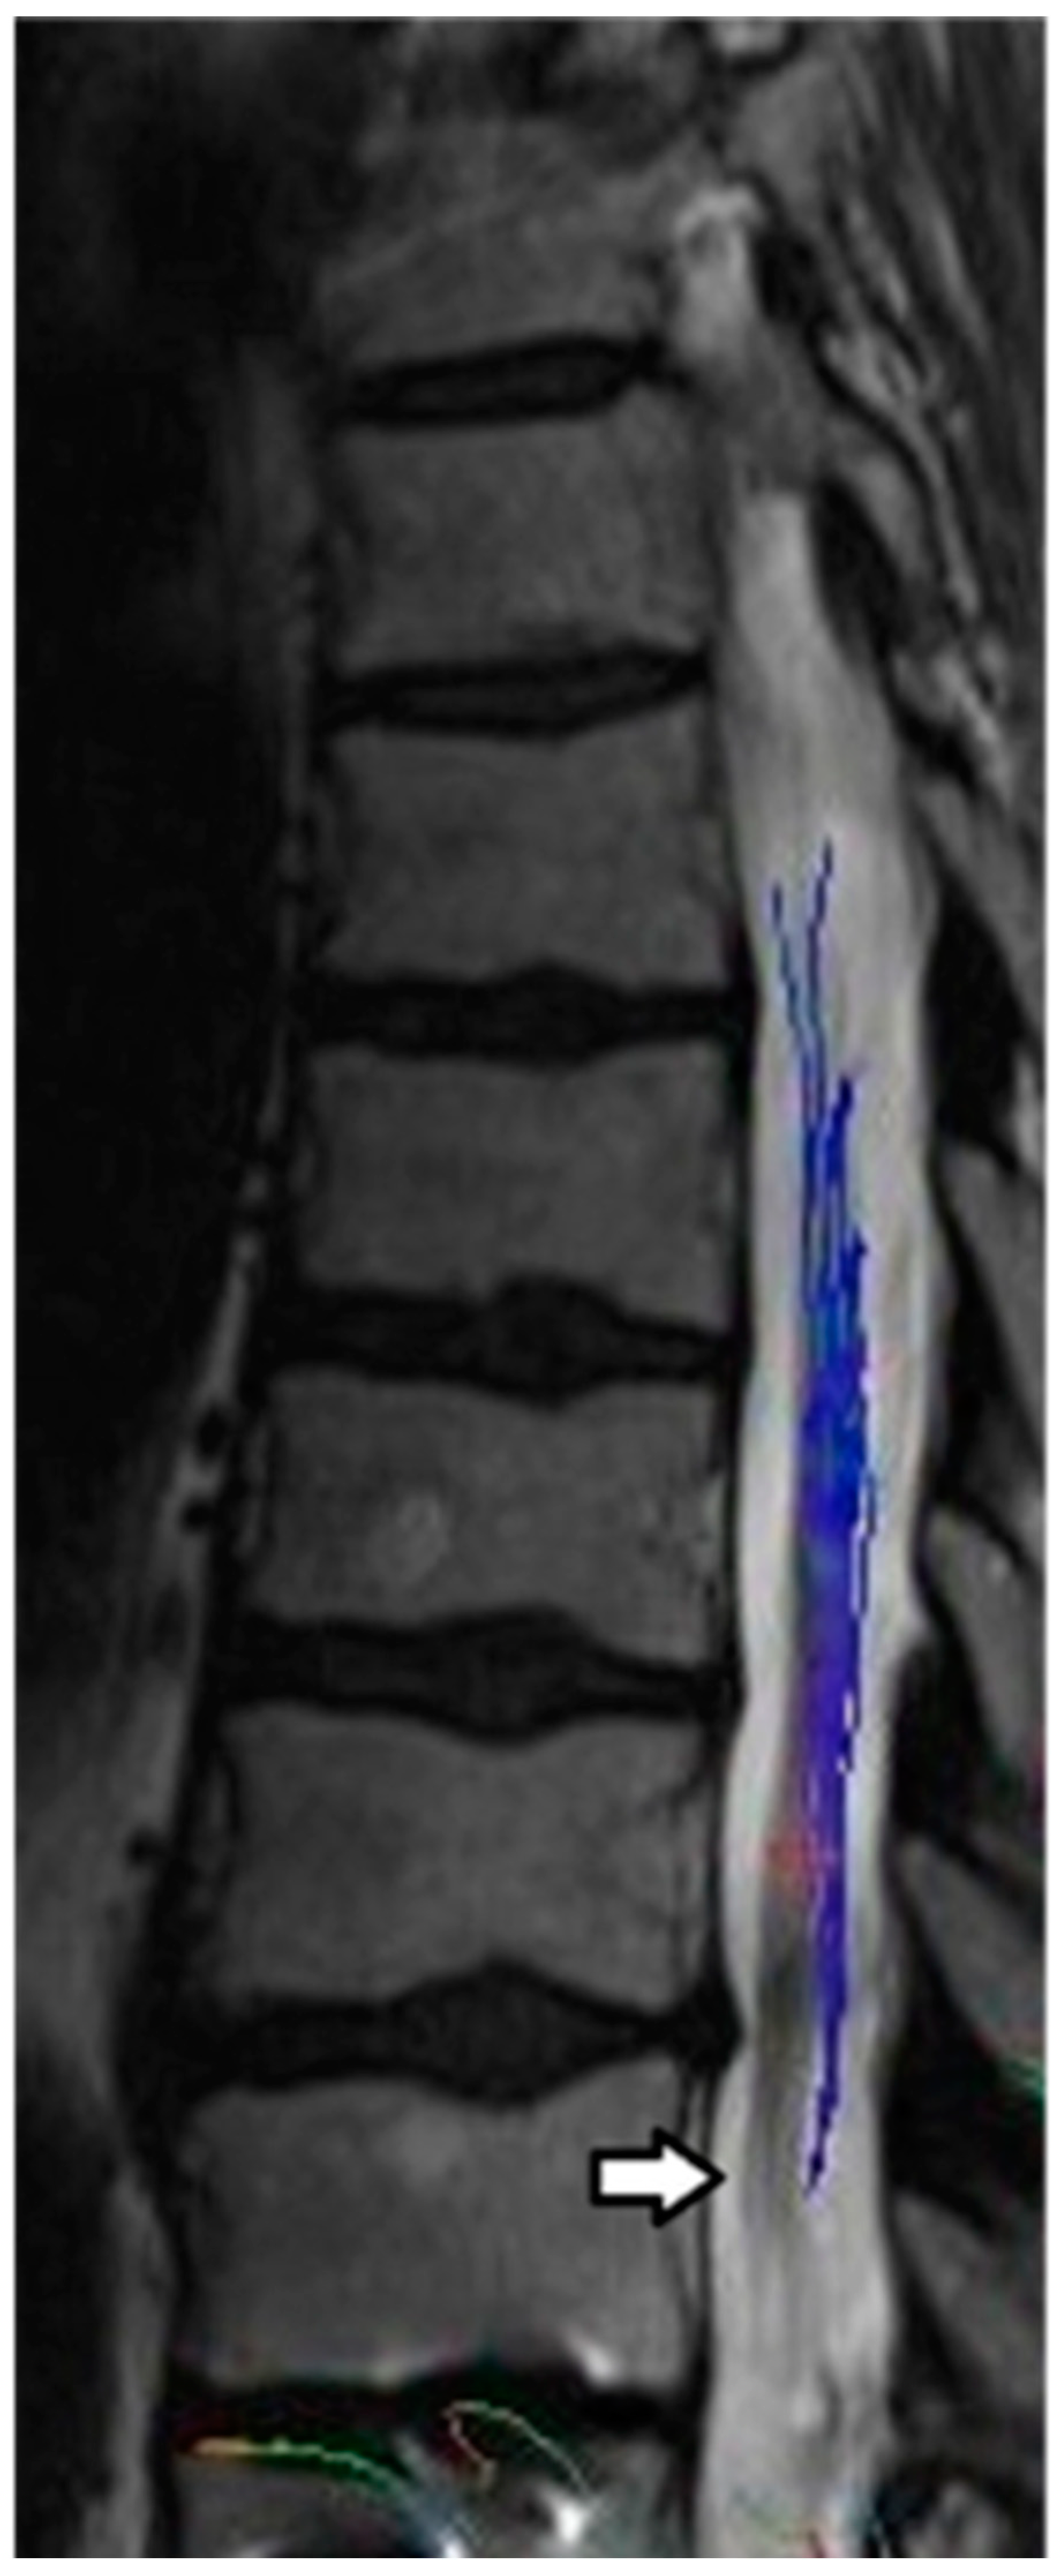

All four subjects were able to complete baseline and one-year MRI studies. All four subjects attended their scheduled appointments. Representative MRI images are presented in Figure 1 and Figure 2.

Figure 1.

Sagittal T2 image demonstrating cord hyperintensity and volume loss proximal to the level of the TSCI (arrow). Cord T2 hyperintensity at the level of T11 vertebra corresponds to a neurological deficit found during the clinical exam. Metallic artifacts within the T11 and L1 vertebral bodies related to orthopaedic hardware from prior posterior decompression and fusion was observed. There is also a chronic anterior compression fracture of T12 noted.

Sagittal T12 post processing MRI diffusion tractography imaging (DTI) demonstrates tapering of tract fibers in the lower thoracic cord proximal to the level of injury, corresponding to the volume loss, in keeping with Wallerian degeneration.